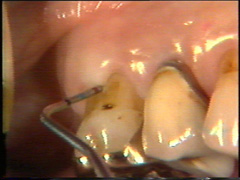

Varón de 50 años de edad que es enviado para tratamiento periodontal., nos comenta que ha sido tratado por el procedimiento de raspado y alisado radicular durante algún tiempo con un resultado limitado, observamos que tine una buena higiene dental pero las señales de patología periodontal continúan.  La imagen muetra una lesión de furcación profunda en el primer molar superior con tejido gingival  firme (Fibrosis) que limita el acceso al  fondo de la bolsa por el método no quirúrgico y también la presencia de cálculo  subgingival neutraliza la penetración de la sonda en la región  dentogingival.

La anatomía de la lesion de  furcación puede ser difícil de registrar usando la sonda periodontal ordinaria. Una cureta delgada o una sonda doblada para dicho propósito es una gran ayuda para descubrir la morfología de la lesión de furca.